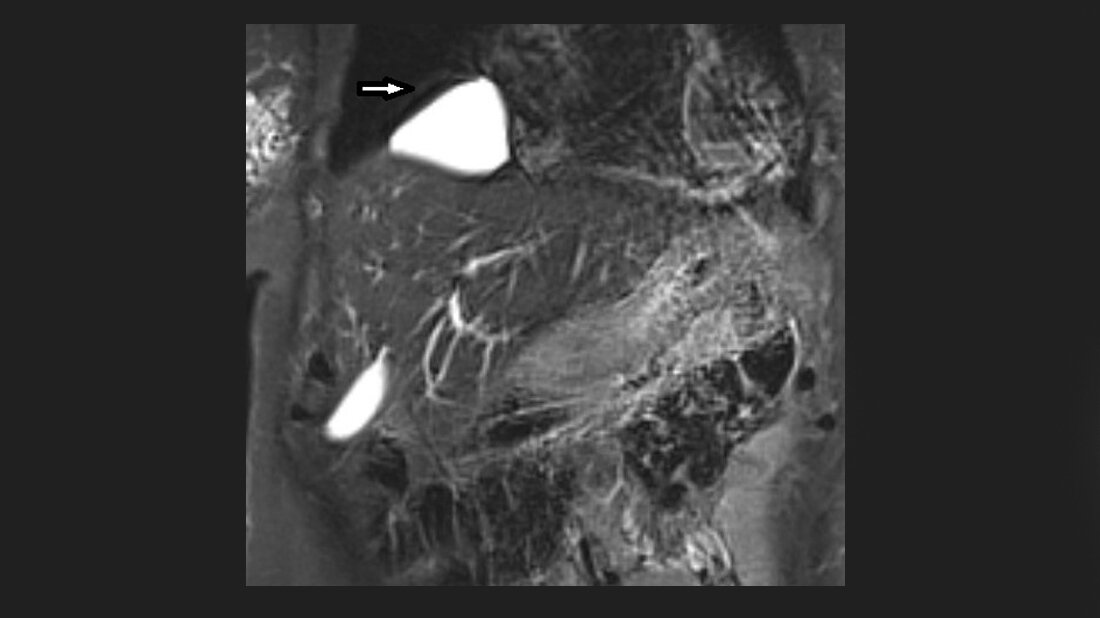

Perikardzysten sind selten vorkommende gutartige Raumforderungen, die Inzidenz beträgt etwa 1 : 100.000. An den mediastinalen Tumoren haben sie einen Anteil von circa 7 %. Mehr als 50 % der Perikardzysten sind asymptomatisch, sie können aber auch für Atemnot, retrosternale Schmerzen und Dysphagie verantwortlich sein, abhängig von ihrer Lage und Größe [6]. Spontane Rückbildungen und auch Spontanrupturen wurden beschrieben.

Perikardzysten und auch parasitäre Zysten des Herzens sind selten. Perikardzysten zeigen im CT und MRT die typischen Kriterien der einfachen Zysten.